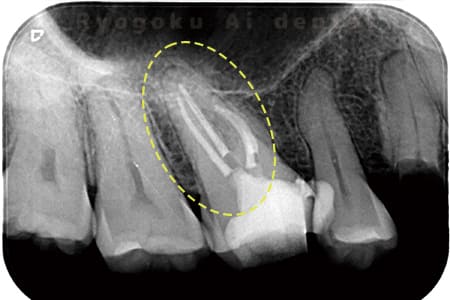

Case02

- 原因

- 慢性根尖性歯周炎

- 治療期間

- 3ヶ月

- 治療内容

- マイクロエンド

- 治療費用

- 121,000円

噛むと痛みが出る、とのことで来院した患者様です。他院での根管治療を終えてましたが、根尖病変を認めるため、マイクロエンドを行いました。